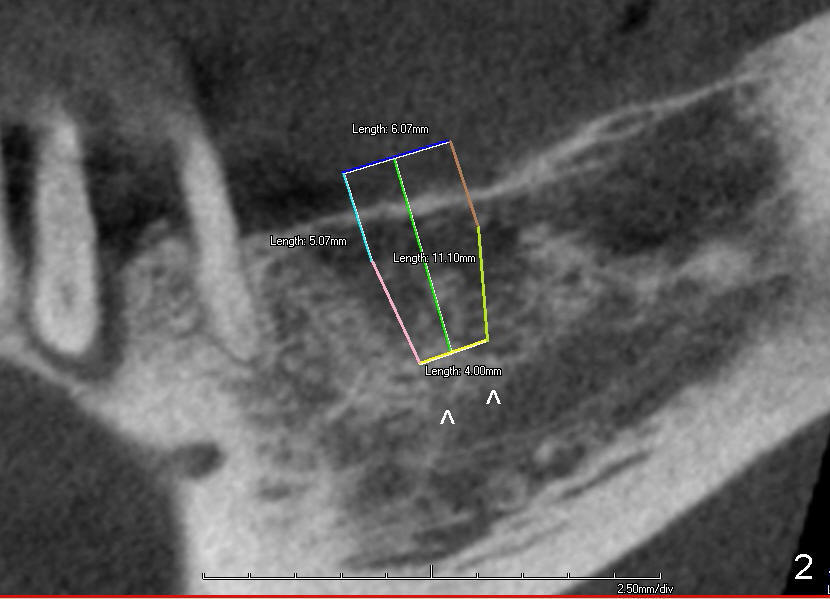

CBCT studies show that a 6x11 mm implant can be safely placed at the site of the tooth #30 (Fig.1 (coronal), 2 (sagittal section). Osteotomy is initiated by 2 mm pilot drill at the depth of 8 mm from the crest (the prospective implant is 3 mm above the crest); X-ray is taken with a parallel pin (Fig.3 P). It appears that there is 12 mm of bone from the crest to the upper border of the inferior alveolar nerve canal. The depth of osteotomy is accordingly adjusted to 11 mm below the crest; osteotomy finishes with insertion of 6x14 mm tap (Fig.4); the patient feels pressure while the tap is being inserted. Following further infiltration with Lidocaine, the depth of the osteotomy is intended to increase in order to bury the implant deeper, because the coronal portion of the buccal plate starts to perforate. The patient feels pain. Finally a 6x14 mm implant is placed ~ 1 mm above the inferior alveolar canal (Fig.5). As mentioned earlier, the rough surface of the implant is exposed buccally (Fig.6 between arrowheads). The nearby buccal plate is decorticated (Fig.7). The autogenous bone harvested during osteotomy (Fig.8) is going to be placed over the exposed portion of the rough surface of the implant (Fig.9); the graft is covered by collagen dressing (Fig.10). The buccal and lingual flaps are approximated with sutures mesial and distal to the implant (Fig.11). To increase the retention of perio dressing, a 4x3 mm abutment is placed.